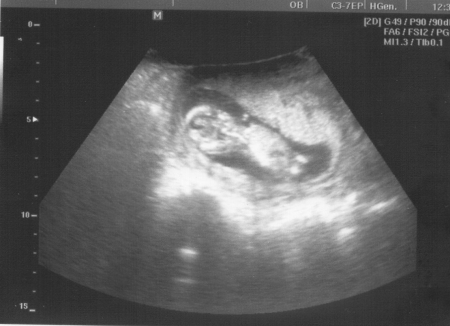

Plod o velikosti 81 mm ve 14. týdnu těhotenství (13+5)

Délka plodu je na konci 14. týdne asi 8 – 9 cm. Hmotnost plodu se pohybuje kolem 25 - 30 g.

Na konci třetího měsíce jsou některé svaly natolik vyvinuté, že se dokáží stáhnout. Pohyby těla jsou ale ještě natolik slabé, že je matka zatím nepociťuje. Na druhé straně plod již aktivně reaguje na mechanické podráždění. Pohyby je možné pozorovat během vyšetření ultrazvukem.

Autoři: Texty na základě zdroje www.babyonline.cz, vlastní praxe a znalostí zpracovala MUDr. Jarmila Halová, doplnil a upravil MUDr. Ondřej Šimetka, přednosta Porodnicko-gynekologické kliniky FN Ostrava, kde byly rovněž pořízeny ultrazvukové snímky, autor: MUDr. M. Pětroš. Poslední korekturu v srpnu 2024 provedla: MUDr. Veronika Ťápalová (Gynekologicko-porodnická klinika LF MU a FN Brno).